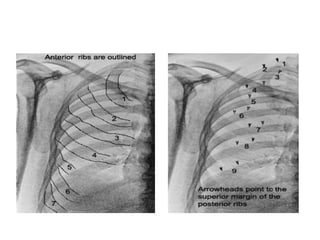

G. BONY STRUCTURES:

• RIBS

F. HIDDEN AREAS: Apices:Partially obscured by ribs, costal cartilage, clavicles & soft tissues  Central lesions obscured by mediastinum and hila  Posterior & lateral basal segments of lower lobes & posterior sulcus obscured by the downward curve of the posterior diaphragm  Hidden areas due to bones

G. BONY STRUCTURES: •RIBS • SCAPULA • CLAVICLES • SPINE • STERNUM